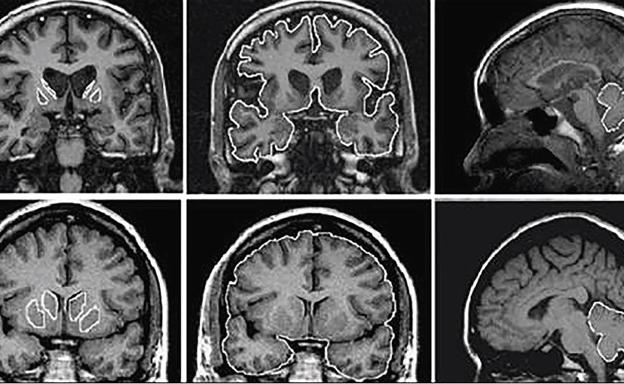

El científico británico recibió el Nobel de Fisiología o Medicina en 2002 por su contribución a la comprensión del mecanismo que permite a los genes controlar la división y la muerte celular a fin de conformar un organismo completo